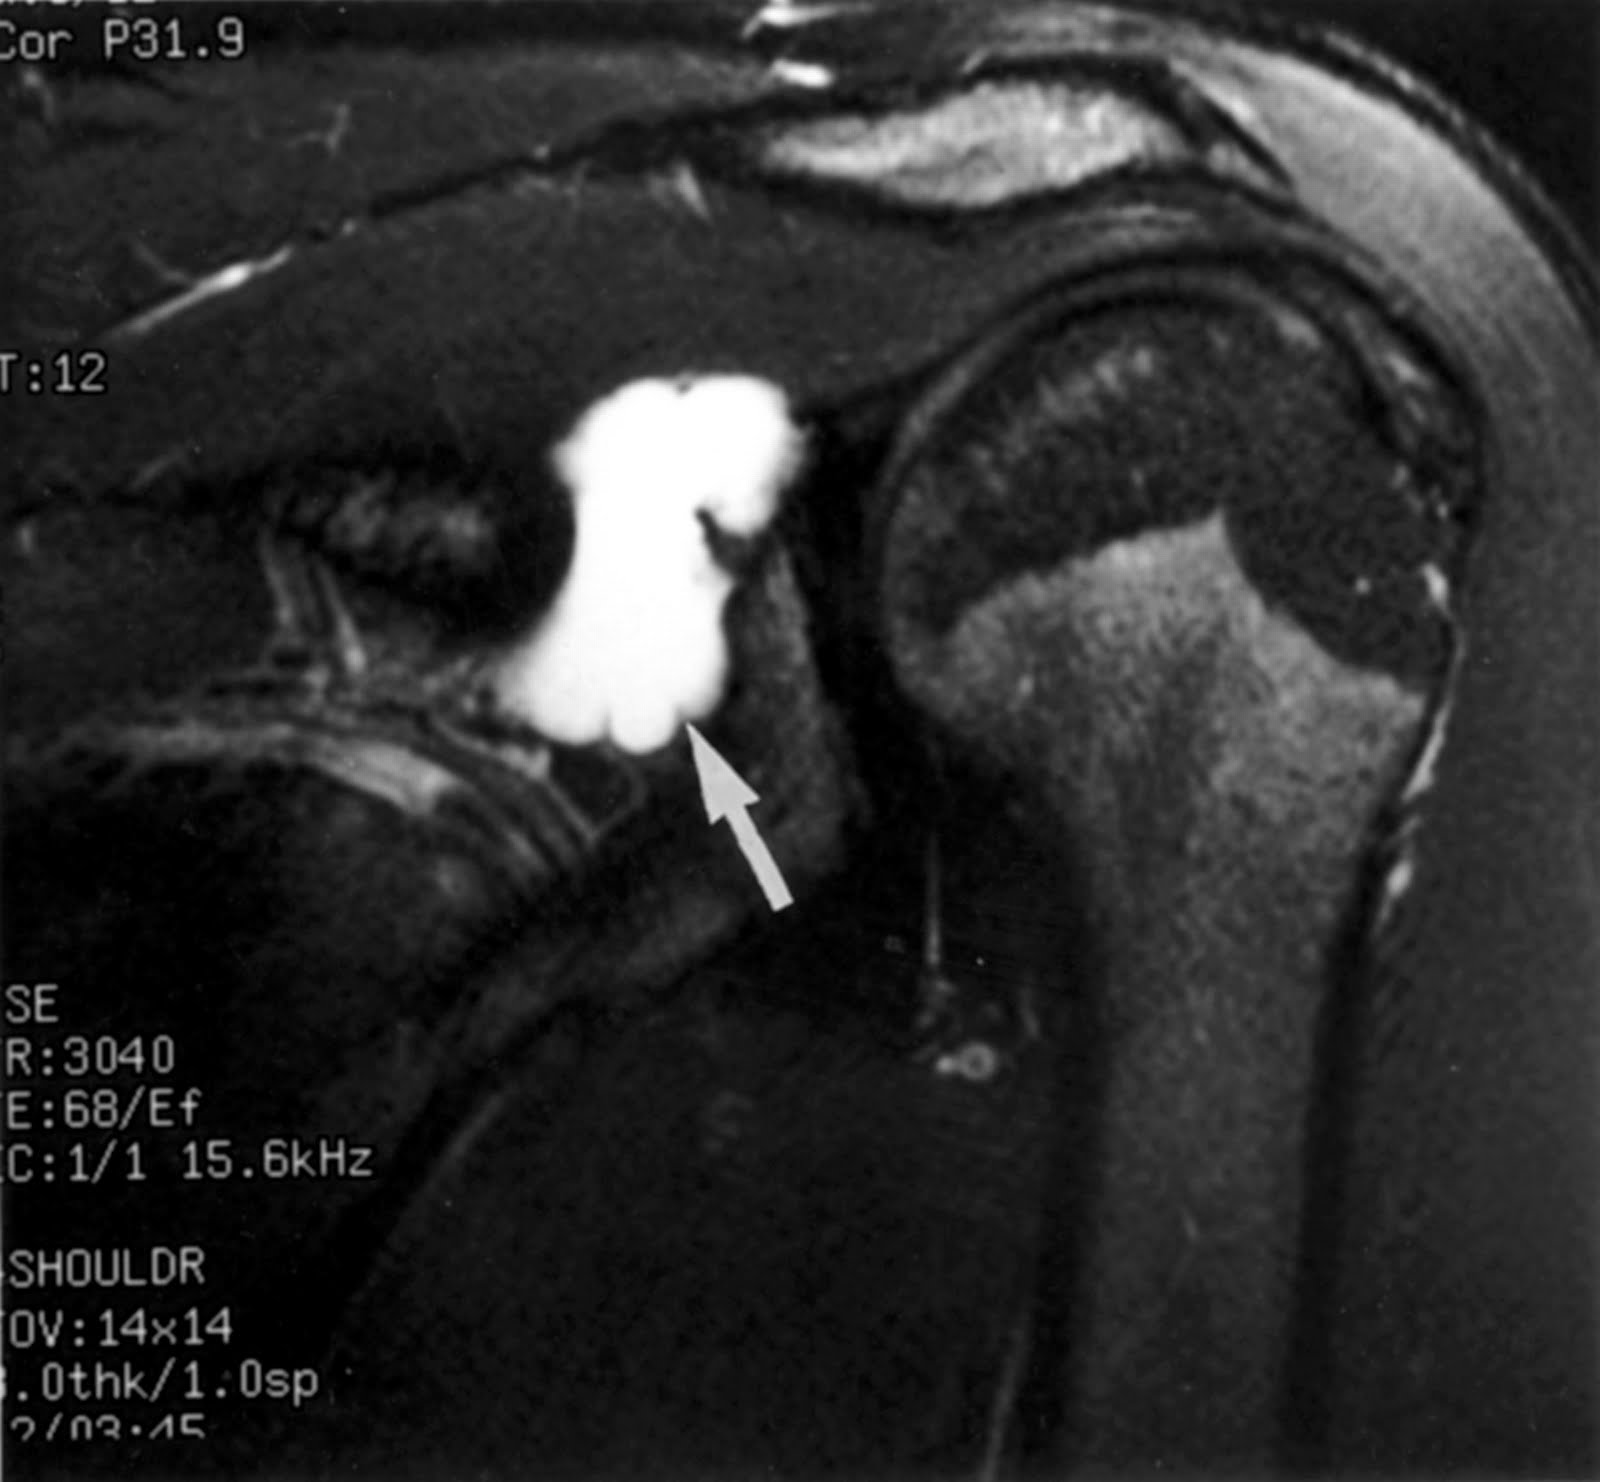

An examination is typically performs through physical examination along with either an ultrasound, x-ray or MRI. If necessary, fluid may be removed from the cyst to be examined.